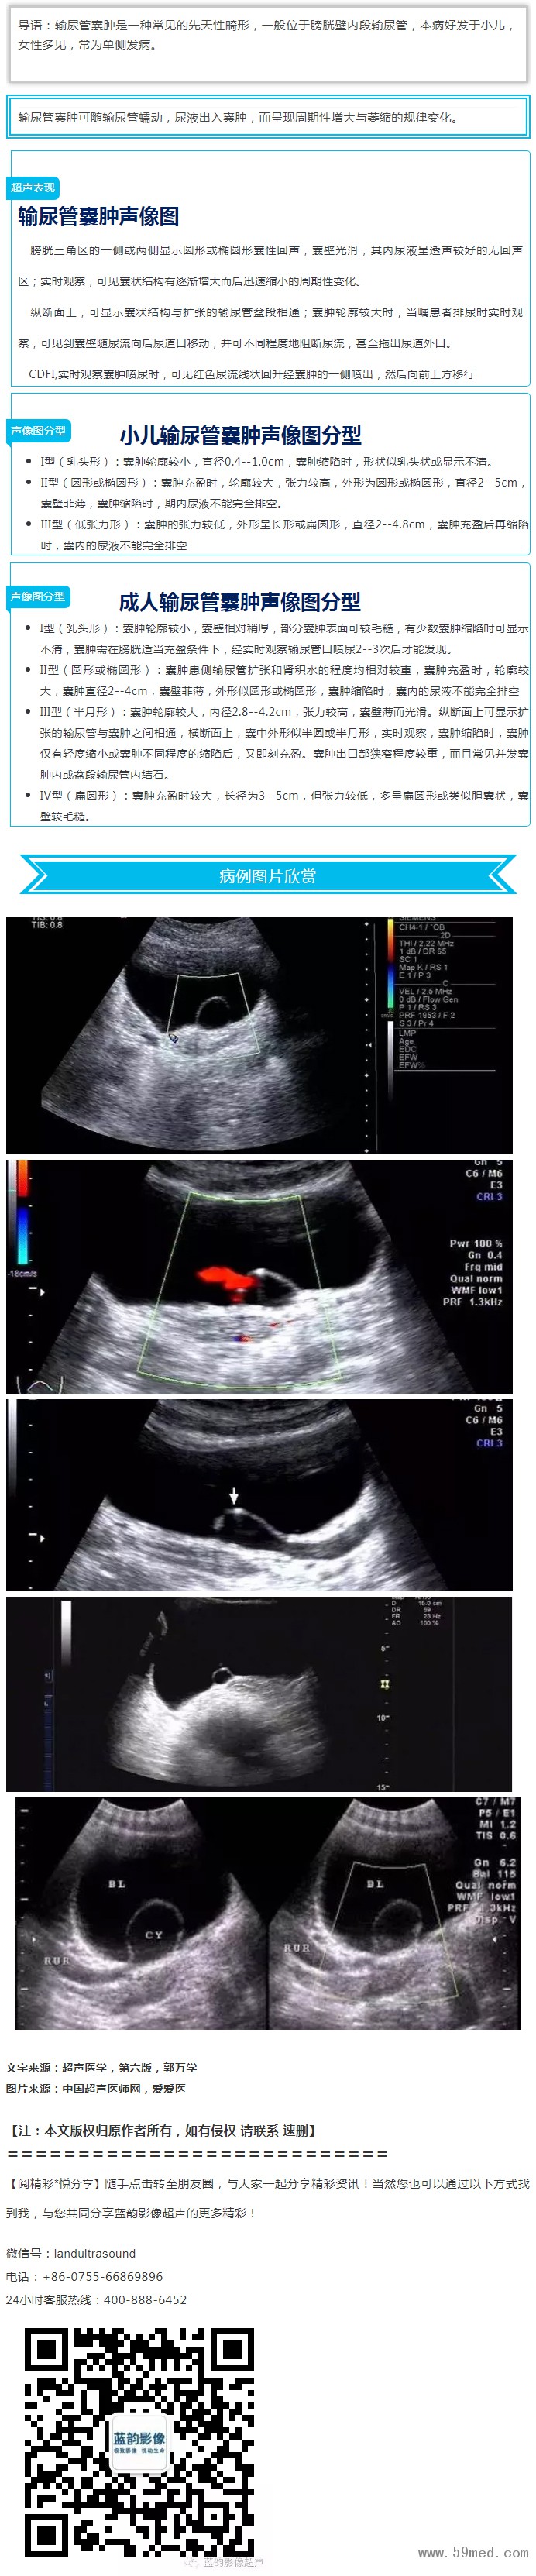

【超聲微課堂】輸尿管開(kāi)口囊腫的超聲診斷